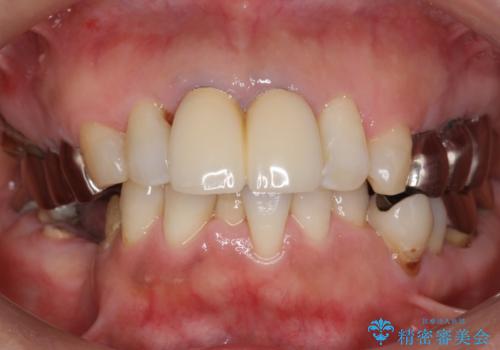

- 虫歯と歯並びを治したいとご希望された患者様です。

またその手前の歯(左下4)は頬側転位していることを気にされておりました。

矯正をおすすめしましたが希望されず、最小限の方法で虫歯と歯並びを治したいとのことでした。

患者様のご希望により、セラミッククラウンにより可及的にう蝕除去後の補綴及び歯並びの改善を行いました。